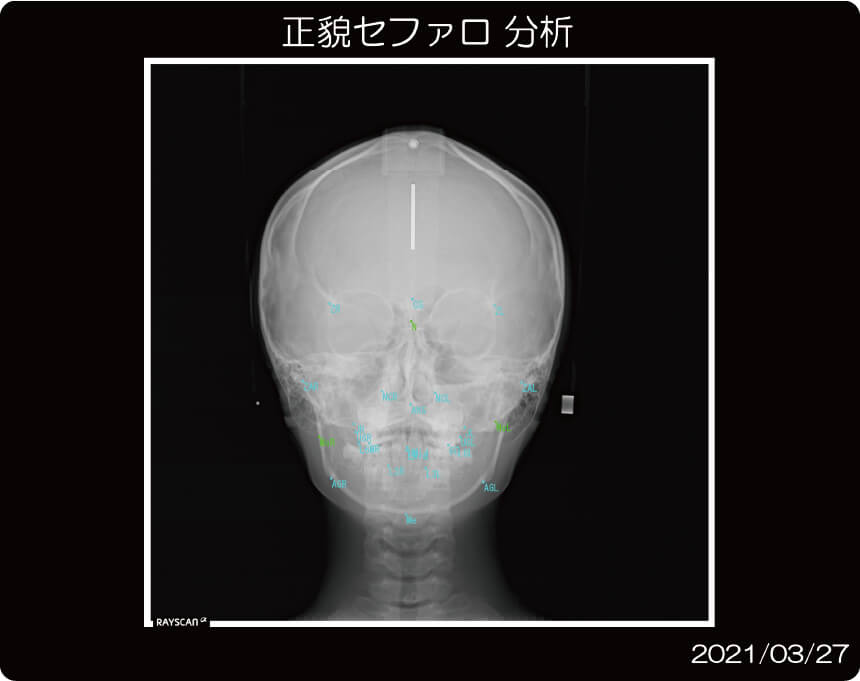

セファロは、矯正治療に必要とする透過性の高い画像を撮影することができます。

多彩な分析機能を備えており、治療前、治療中、治療後の歯の動きが詳細にわかりますので、

患者様お一人おひとりに最適な治療計画をご提案することができます。

トレースの作成や線分析・角度分析などの各種分析が可能です。